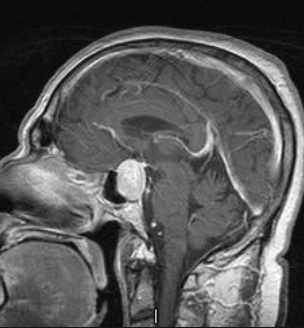

3、磁共振成像(MRI)。MRI可以用来测量肿瘤的大小。一种叫做钆的不同染料会在扫描前使用,以产生更清晰的图像。MRI比下面描述的计算机断层扫描(CT)更能诊断大多数垂体肿瘤。因此,MRI现在是国际标准的诊断测试。